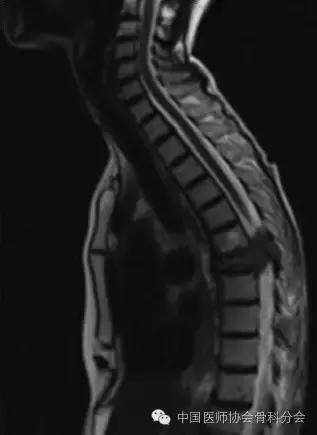

图1. 病例1.术前矢状面的T2加权像(上)和横断位增强后的T1加权像(下)的磁共振图像显示胸7压缩性骨折伴硬膜外病变压迫脊髓